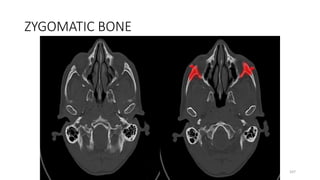

ZYGOMATIC BONE